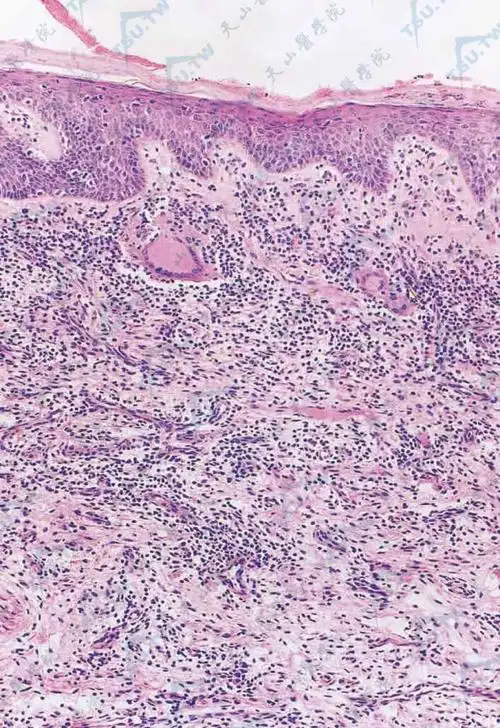

肉芽肿性皮肤松弛症